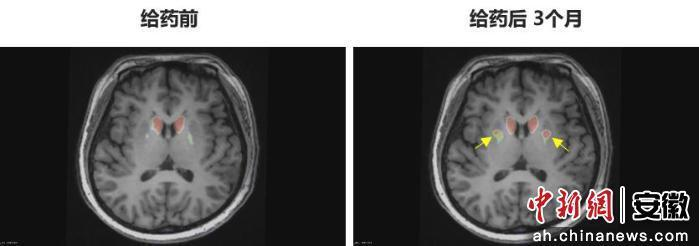

今年6月,李女士在中國科學技術大學附屬第一醫院接受了NCR201干細胞移植治療,該療法利用誘導多能干細胞(iPSC)衍生的多巴胺能神經前體細胞。三個月后,她成為全球首例“功能性治愈”的帕金森病患者。

“身體不僵硬了,像正常人一樣。”李女士笑著說。多年的抖動與“關期”徹底消失,她重新感受到身體的輕盈和心靈的自由。術后影像顯示,移植細胞已在腦內成功定植并發揮功能,醫生稱這些“亮點”是新生多巴胺能神經元的直接證據。